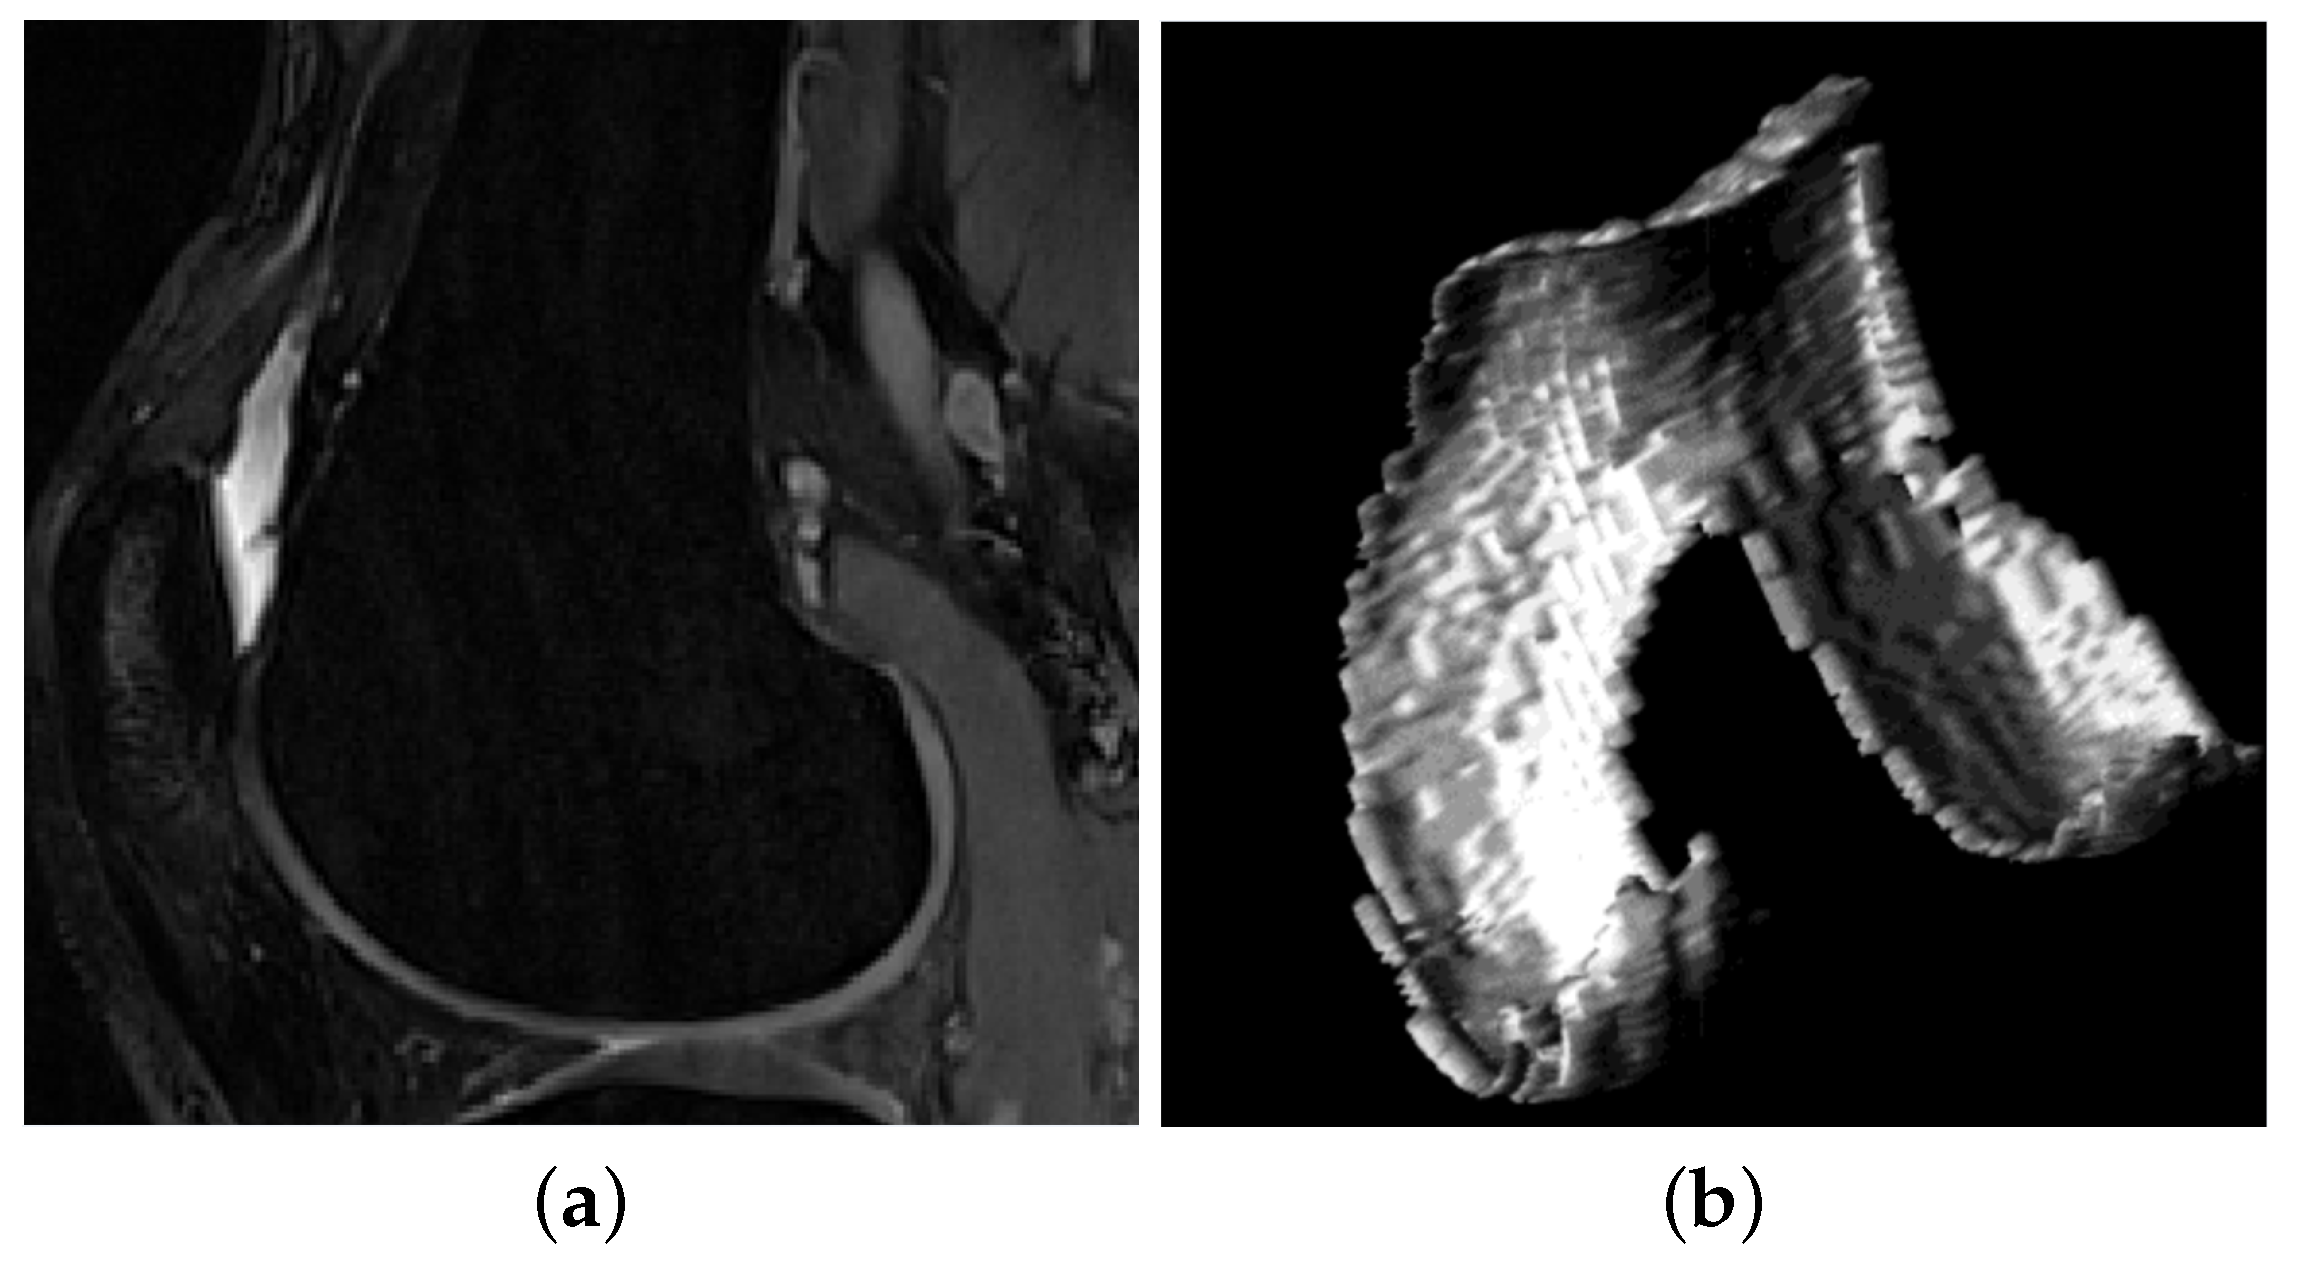

3.2. Comparison of Different Surface Models